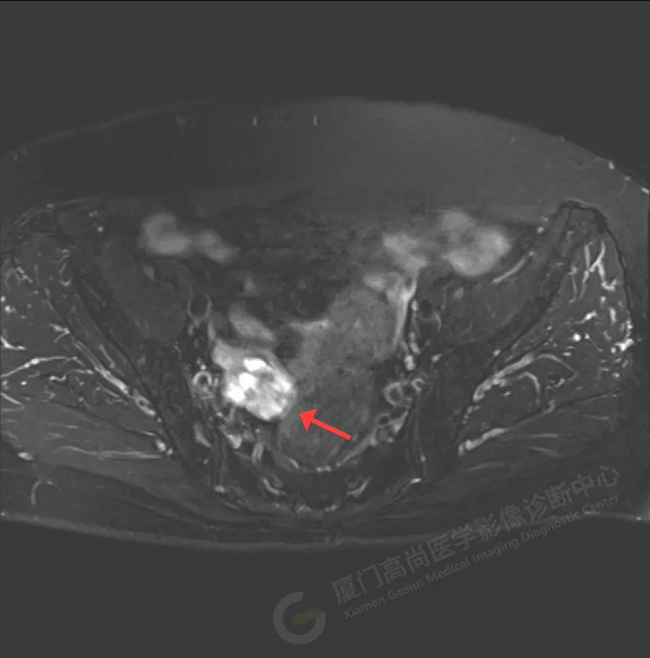

磁共振影像圖

初步診斷:右側附件區(qū)囊實性占位伴腫大淋巴結,考慮卵巢來源惡性腫瘤,卵巢Ca可能性大。為進一步明確病灶良惡性、大小、是否有轉移,吳阿姨在我中心進行了PET/CT檢查。